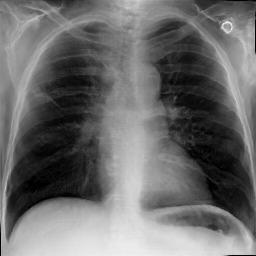

Image Reconstruction. Table 1 shows that the co-training scheme outperforms the \mathcal{E}-training approach in reconstruction accuracy, as indicated by higher PSNR and IW_SSIM scores, highlighting the benefits of joint optimization for enhancing reconstruction quality. The results are further validated by the visual comparison in Fig. 2, where the co-training scheme recovers input images with finer details and higher fidelity. In contrast, the \mathcal{E}-training scheme exhibits noticeable discrepancies when compared to the original images.

Refer to caption

XRX_{R}

Co-training

\mathcal{E}-training

Fig. 2: Reconstruction results. The first row displays the real images XRX_{R}. The last two rows show the reconstructed images X^R\hat{X}_{R} produced by the proposed co-training scheme and the \mathcal{E}-training scheme, respectively.